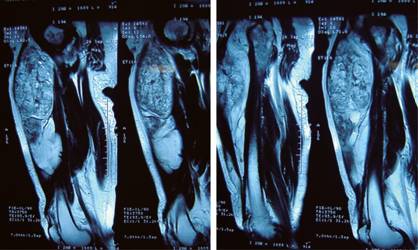

A nivel del muslo, se encontró aumento de volumen en su tercio medio, no doloroso ni fijo a partes óseas, pero de dimensiones importantes, por lo que se comunicó a la paciente la necesidad de tomar otro tipo de exámenes, entre ellos la resonancia magnética del muslo para llegar a un diagnóstico más certero y programar la cirugía para retiro del mismo (Figura 1).

La resonancia magnética mostró presencia de masa tumoral profunda de grandes dimensiones que involucraba el tercio medio y proximal del muslo en la superficie anterior, sin datos de malignidad y bien delimitado.